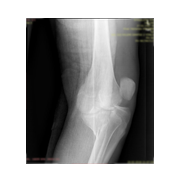

Görüntüleri büyütmek için resmin üstüne tıklayınız.